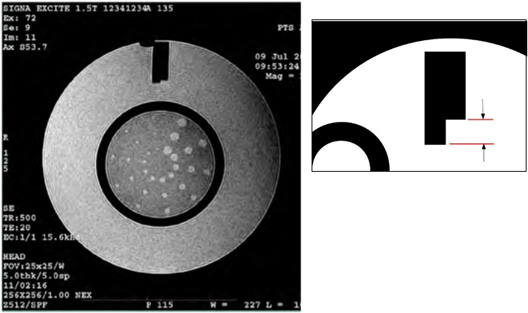

Slice Thickness Accuracy (8HRBrain Coil)

The ACR MRI phantom contains a horizontally oblong structure (in the center CORONAL plane) called the slice thickness insert within which there are 2 horizontally oriented signal ramps. The length of these 2 ramps will be measured and used to calculate the slice thickness in mm.

Figure 16. Slice Thick Ramps ROI Placement

Figure 17. Slice Thick Ramp Distance Measurements

Calculate the slice thickness using the following formula:

slice thickness = 0.2 x (top x bottom) / (top + bottom)

where top and bottom refer to the ACR T1 Top Ramp Length (mm) and ACR T1 Bottom Ramp Length (mm) respectively.

If both the ACR T1 & T2 series slice thicknesses are equal to 5.0mm ±0.7mm, the Slice Thickness Accuracy Test has passed.